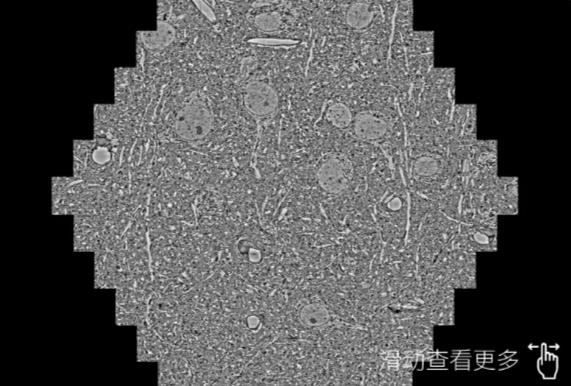

鼠脑切片。左图使用珠海蔡司珠海扫描电镜MultiSEM706对165μmx143pm面积区域成像,耗时仅需1.5秒。右图为鼠脑切片中30μm区域放大效果。样品由芝加哥大学B.Kasthuri提供。

使用蔡司高速珠海扫描电镜MultiSEM对1mm²人脑皮层组织进行高分辨成像,并对其中的各种细胞结构进行三维重构分析。左图展示了2x3mm²组织平面中锥体神经元的三维重构效果。右图显示了局部体积神经元三维重构。图像由哈佛大学chtman实验室提供,渲染图由D. Berger 制作。